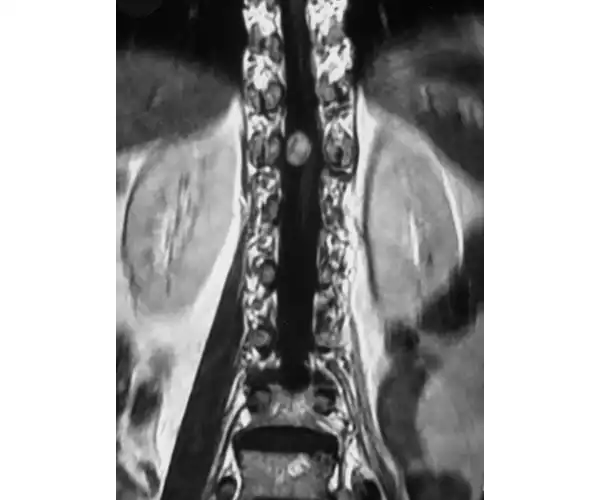

MRI Showing Tumour

N5 Spinal Cord Tumours